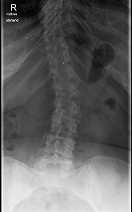

Röntgenbilder

- Dateianhänge

-

- LSPINE

- unbenannt nochmal verkleinert.png (25.52 KiB) 19770 mal betrachtet

deine Bilder lassen vermuten, dass vielleicht gar nicht die Skoliose dein Problem ist, sondern dein sagittales Profil. (Steht dein Kopf ziemlich nach vorne, wenn du dich vin der Seite betrachtest?) solltest auf jeden Fall einmal zum Spezialisten, im deine Situation kompetent abklären zu lassen. Aus NRW ist wahrscheinlich Dr. Verres in Bingen am nächsten.

mit dem sagittalen Profil meint man das Profil von der Seite gesehen. Laut deinen Aufnahmen hast du eher eine geringe Skoliose, aber einen ziemlichen Rundrücken und Hohlkreuz was auch Beschwerden machen kann und das die Ärzte auch gerne übersehen oder nicht sehen wollen. Deshalb ist es auch wichtig, einen Spezialisten aufzusuchen, der dies auch mit behandeln kann. Leider ist dies keine Ganzaufnahme, dann würde man das eher sehen. Es gibt hier schon genug Berichte, die das mit Hyperkyphose und -lordose gut beschreiben. Also lesen bildet...

Dem kann ich mich nur anschliessen, es sieht sehr nach Rundrücken (Bild 2-Hyperkyphose) und Hohlkreuz (Bild 1-Hyperlordose) aus.sloopy hat geschrieben:deine Bilder lassen vermuten, dass vielleicht gar nicht die Skoliose dein Problem ist, sondern dein sagittales Profil.